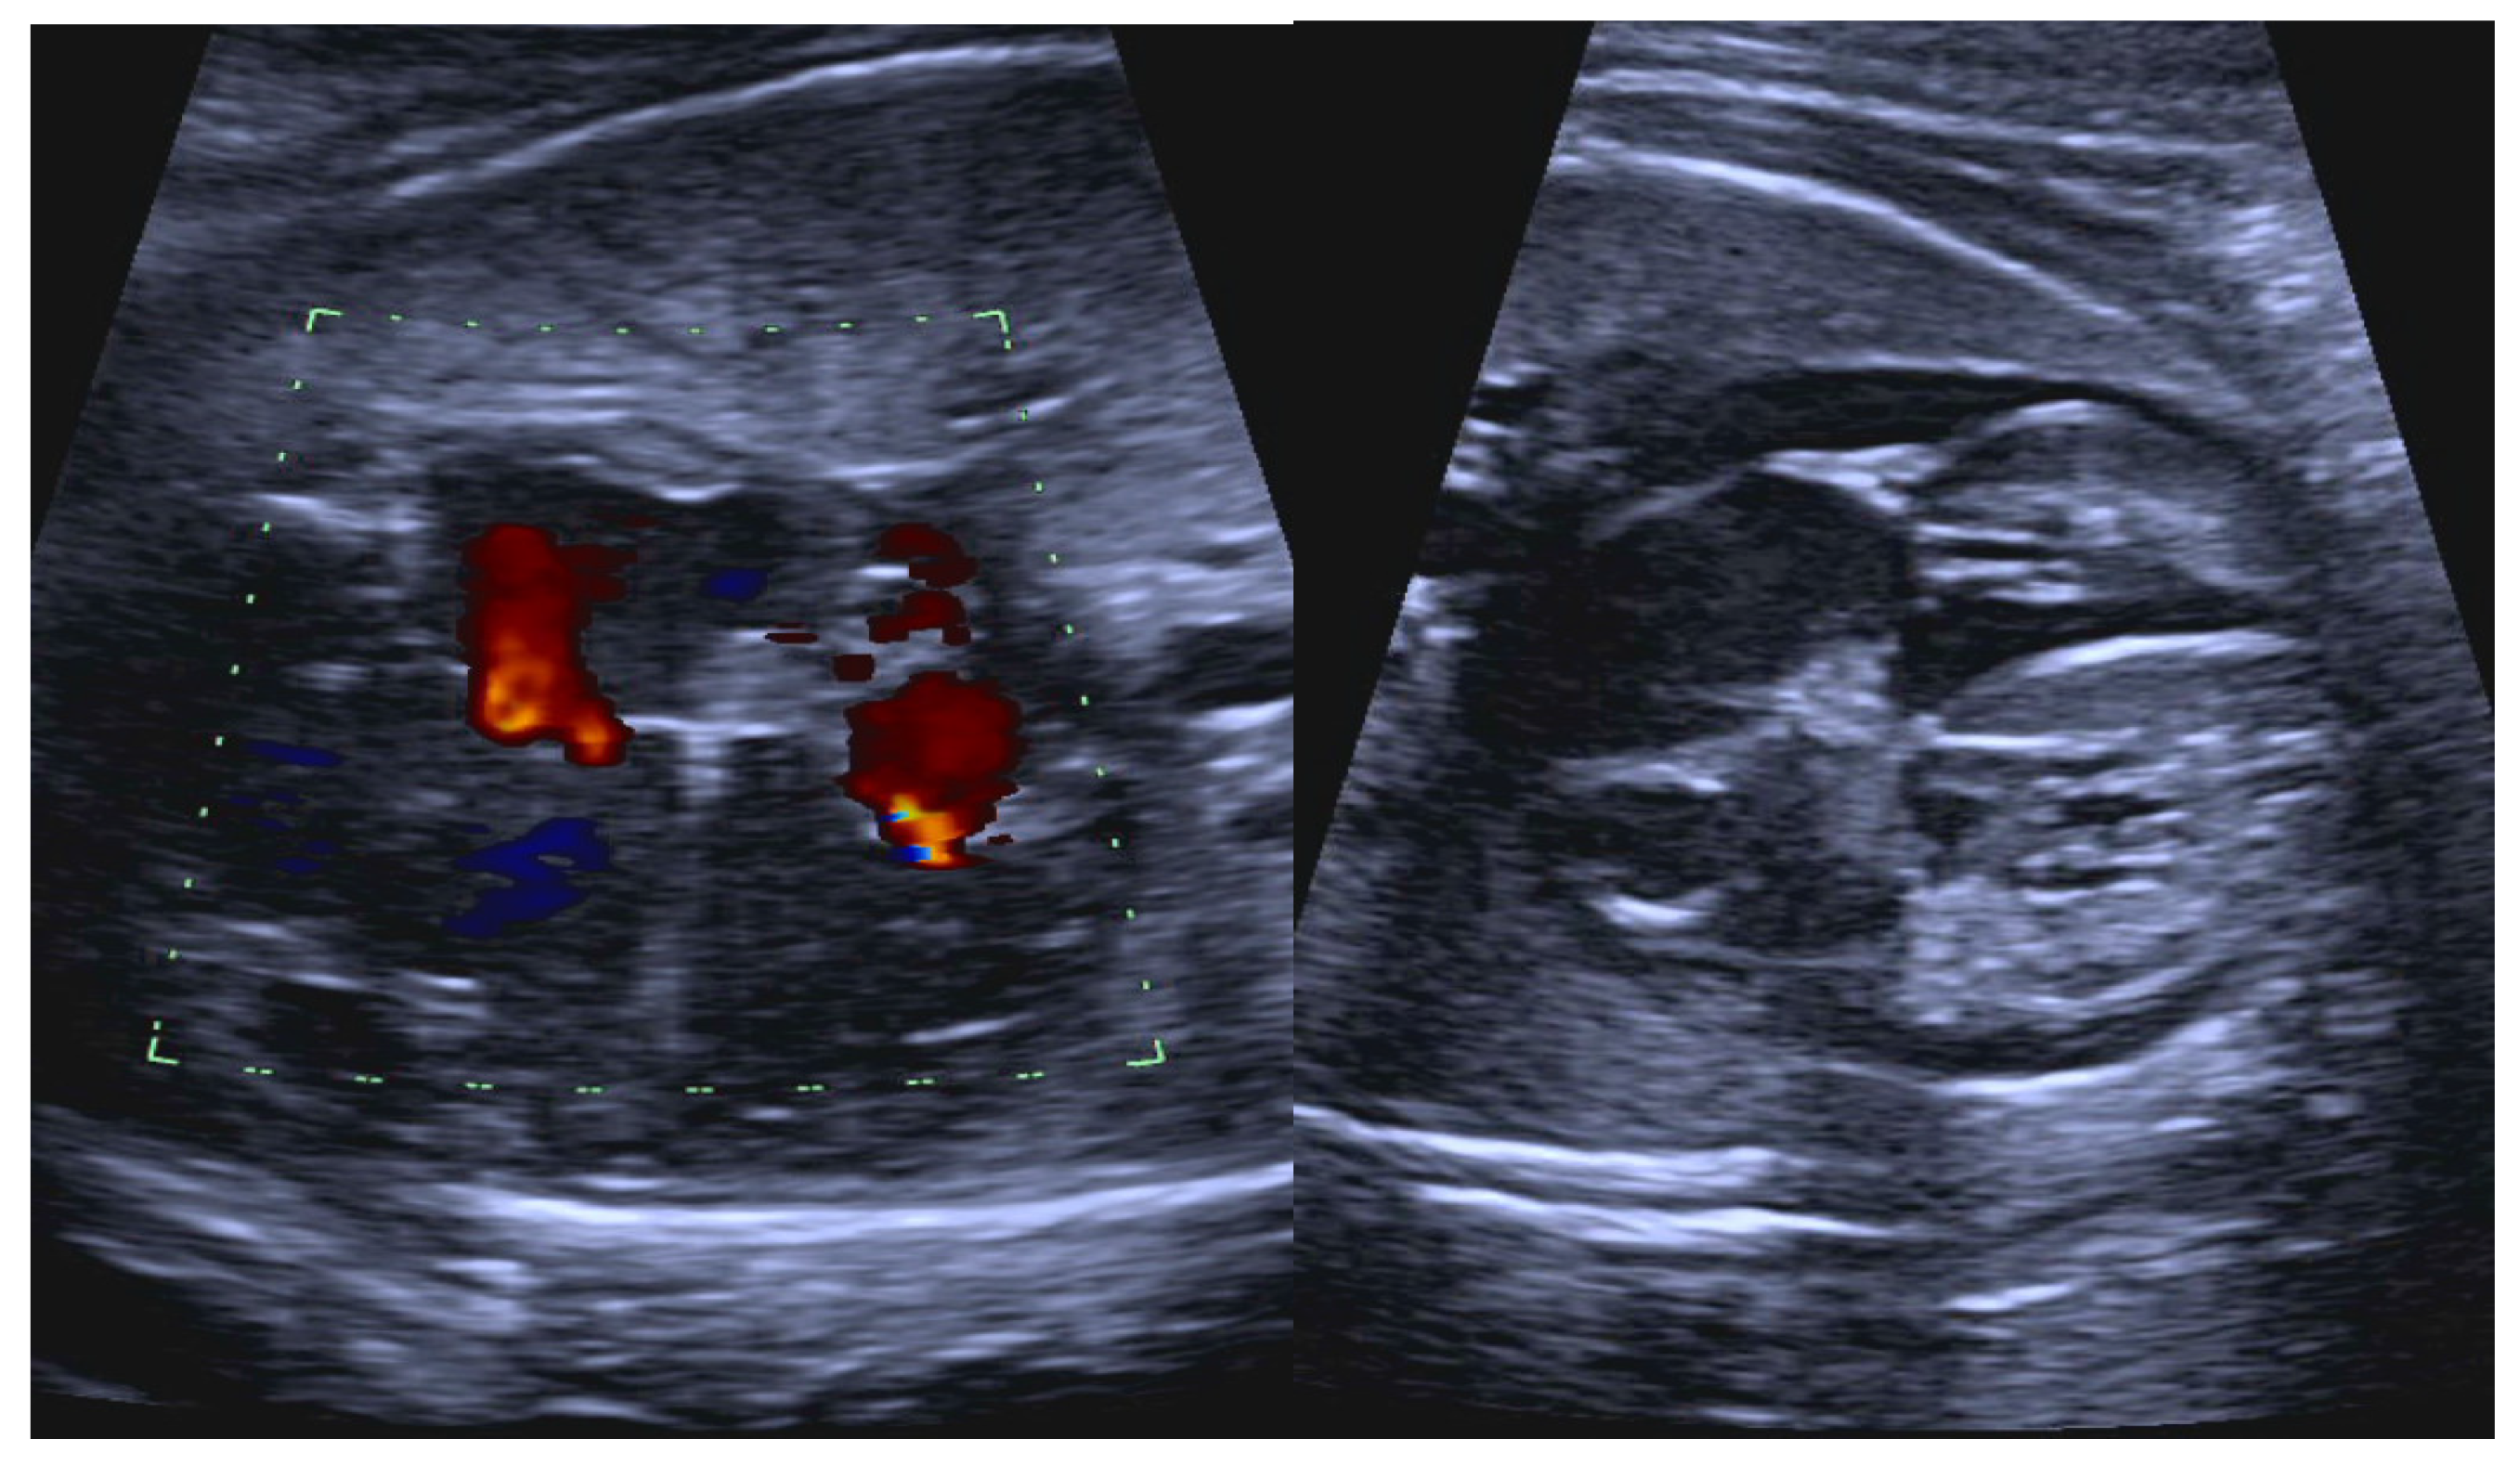

- Short VA SVT (Figure 3 and Figure 4) demonstrates a ventricular–atrial (VA) interval that is less than half of the ventricular–ventricular (VV) interval (VA:AV ratio < 1) and a sudden onset and termination of tachycardia; tachycardia usually terminates with a non-conducted atrial contraction. Short VA SVT includes AVRT (also known as orthodromic reciprocating tachycardia, ORT) and atrioventricular nodal reentrant tachycardia (AVNRT). Short VA SVT typically presents after 18 weeks of gestation.

- Long VA SVT (Figure 4) demonstrates a VA interval that is more than half of the VV interval (VA:AV ratio > 1). Long VA SVT includes EAT and PJRT. A distinguishing feature of EAT is tachycardia termination with ventricular contraction. Long VA SVT may occur as early as 12 weeks of gestation. Because long VA tachycardias have slower rates, they are less likely to cause hydrops.